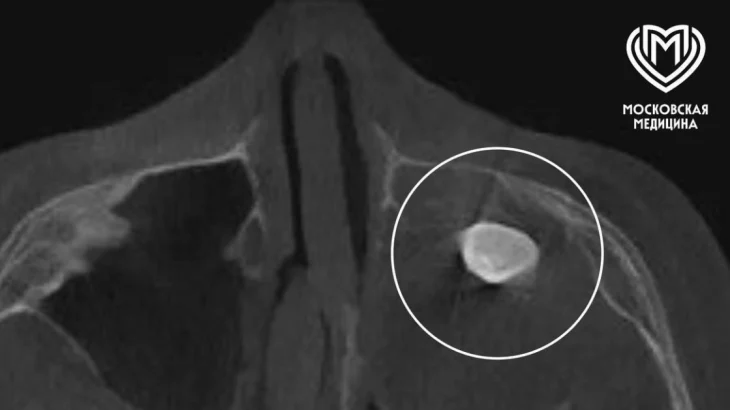

Хирурги Филатовской детской больницы Москвы удалили 15-летнему подростку зуб, который вырос в носу. Об этом во вторник, 17 марта, рассказали в столичном департаменте здравоохранения.

Мальчик обратился с жалобами на асимметрию лица и заложенность носа. Выяснилось, что в другой клинике у подростка в гайморовой пазухе нашли сформированный зуб, после чего предложили его удалить.

- Мальчику нужно было провести операцию по Колдуэллу-Люку. Сделав разрез, врачи обнаружили новообразование, внутри которого и находился зуб, - добавили в Telegram-канале ведомства.